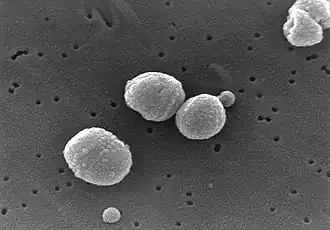

Étiologie

Les pneumonies aiguës sont, le plus souvent, des infections bactériennes. On parle de pneumopathie à germe communautaire pour les infections contractées en dehors d'une structure de soin ; il s'agit des plus fréquentes (80 à 90 %). Les germes les plus souvent identifiés sont, par ordre décroissant, Streptococcus pneumoniae, Haemophilus influenzae, Legionella pneumophila et Mycoplasma pneumoniae. Streptococcus pneumoniae est le germe mis le plus fréquemment en cause et associé à des décès précoce[6]. La responsabilité de Mycoplasma pneumoniae est plus fréquemment établie chez l'enfant ou l'adulte jeune[6]. Legionella pneumophila représente moins de 5 % des pneumopathies infectieuses et plus souvent mis en cause en cas de pneumopathies infectieuses sévères. Chez les personnes âgées, Staphylococcus aureus ou les entérobactéries représentent 10 % à 20 % des cas[7].